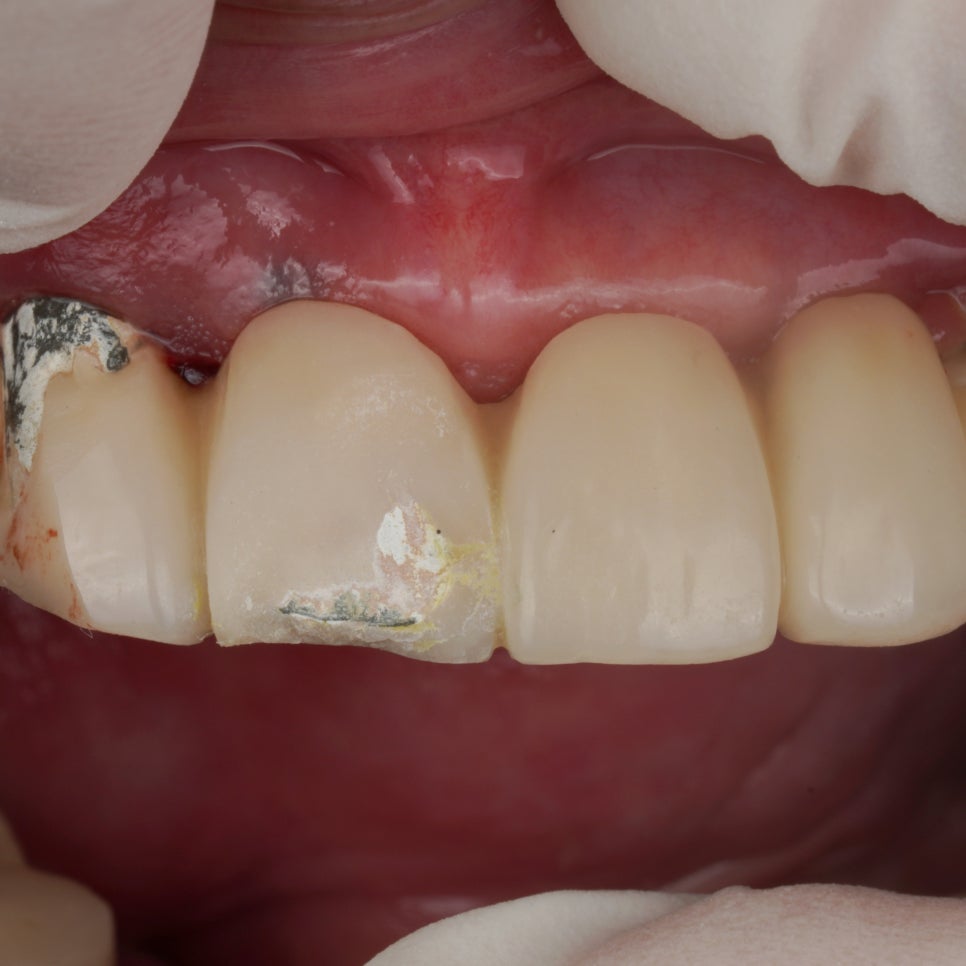

치과의사 선생님이 할머님을 모시고 찾아오셨습니다. 앞니 PFM 도자기 부분이 깨졌는데 레진을 이용해 수리하길 원하셨어요. 보통 그런 경우 크라운 다 제거 하고 재제작해서 넣어드리는 게 좋은데 단일 크라운이 아니고 브릿지인 경우에는 워낙 비용부담이 크기 때문에 앞니 하나만이라도 수리해드리곤 합니다. 물론 크라...

깨져서 오셨고

바로 수리해드렸습니다.

이 사진 보여드리면

보통은 그냥 크라운 다시 만들었겠거니,

하고 생각합니다.

진짜 그런지 궁금하시죠?